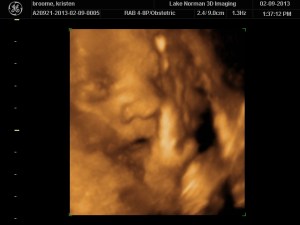

..We meet again, little boy!